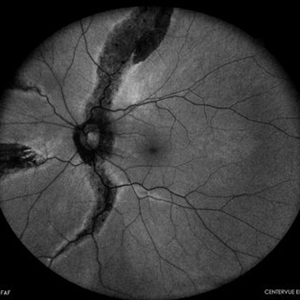

Fundus photograph (autofluorescence) of a 43-year-old myopic man (left eye) Axial length: 29.32 mm

Photographer: Bruno DECAY, MD

Imaging device: iCARE EIDON confocal fundus imaging system (Ultra-Widefield Module)

Condition/keywords: Bilateral, High myopia